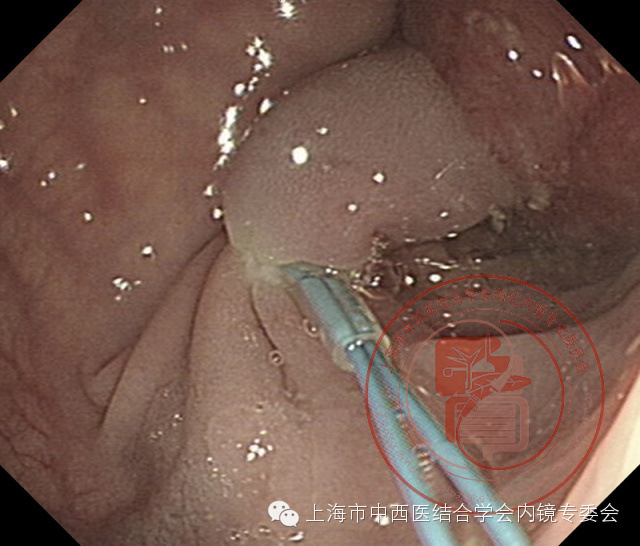

亚蒂息肉尼龙套扎操作

内镜抵达病变区域时,助手递上安装好的尼龙圈套释放器,操作者将尼龙圈套释放器顺内镜钳道插入。当视野内可见塑料外套管先端部时,嘱助手将尼龙圈套器从塑料外套管内缓慢伸出(注意:尼龙圈套不宜过长伸出塑料外套管,否则尼龙圈套器尾端容易从金属拉钩上脱落)。尼龙圈套器对准隆起病变基部套入,确认位置是否满意,一旦满意嘱助手缓慢向外推出塑料套管至隆起病变基部,紧接着一边缓慢朝助手方向拉移塑料外套管,一边缓慢收紧释放装置,这时可以看到塑料外套管内的塑料固定器向前推移,使尼龙圈套器逐渐缩小,直至收紧隆起病变基部,病变表面色泽由橘红变暗红或紫红色。随后朝助手方向快速拉移塑料外套管,尼龙圈套器尾端与金属拉钩之间迅速脱离,退出释放装置。如果操作者认为尼龙线过长,可以由助手用缝合线剪切器剪断过长的尼龙圈套线。

亚蒂息肉

套扎息肉基部

切除后创面